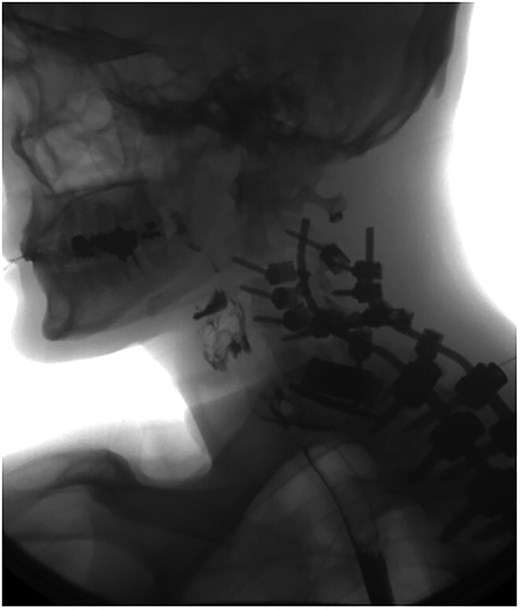

A 35-year-old male presented with a month-long history of dysphagia, severe headache, and posterior neck pain that radiated to the occiput. His medical history was significant for cervical surgeries, including an anterior cervical discectomy and fusion (ACDF) at C5/C6 one year and two months ago (Fig. 1). Shortly thereafter, the patient underwent revision surgery along with posterior plating from C5 to T1 due to osteomyelitis, worsening cervical deformity, and retropharyngeal abscess (Fig. 2). Initial workup included a noncontract computed tomography (CT), demonstrating increased gas density at C6 corpectomy site and post cricoid region (Fig. 3). A swallow study was obtained based on suspicion of a perforation and demonstrated extraluminal leakage of contrast posteriorly at the C6 level, consistent with initial CT (Fig. 4). Surgery included removal of the anterior and posterior hardware and esophageal repair. Although initially the esophageal injury was suspected to be related to the hardware, intraoperatively, it was found the instrumentation was not in communication with the esophagus. This confirmed the perforation was unrelated to direct injury from the cervical hardware construct, which was intact. The esophagus was repaired with a pectoralis flap. The postoperative course was uneventful, and the patient was discharged home after one week. The patient later died due to severe complications of substance abuse unrelated to the operation.

Sagittal T2-weighted MR of prior retropharyngeal abscess that led to revision and posterior plating from C5 to T1.